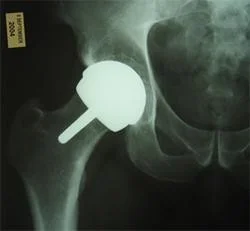

Arthroplasty:

- Joint replacement

- Partial

- Total

Total Joint Arthroplasty:

-

Replacing the native joint with prosthesis

Indicated:

- Old patient with deformed, stiff & painful joint.

Contraindication:

- Young active patients

- Infected joint

- Neuropathic joint

Used:

- All joints.